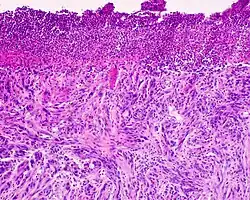

Czerniak szerzący się powierzchownie

Zaawansowany czerniak szerzący się powierzchownie (widoczny wzrost pionowy zmiany)

Obraz histopatologiczny czerniaka szerzącego się powierzchownie

Jest to najczęstszy podtyp czerniaka stanowiący około 70% wszystkich przypadków tego nowotworu[81][82]. Charakteryzuje się promienistym i powierzchownym rozprzestrzenianiem się guza początkowo w naskórku, a w późniejszym etapie w warstwie brodawkowej i siateczkowej skóry właściwej. Czerniak szerzący się powierzchownie może pojawiać się w dowolnej lokalizacji, szczególnie w miejscach wystawionych na intensywną, przerywaną ekspozycję na promieniowanie ultrafioletowe. U kobiet zwykle występuje na kończynach, a u mężczyzn w obrębie tułowia[83].

Makroskopowo jest płaską lub płasko-wyniosłą zmianą z typową asymetrią jej budowy. Zmiana zwykle jest ostro ograniczona, a granica zmiany jest nieregularna, pokarbowana, może przypominać mapę[81][84]. Rzadziej granica jest nieostra[81]. Wykwit jest nierównomiernie zabarwiony, przybiera kolor od ciemnobrązowego do ciemnoczarnego. Szare i białe obszary wskazują na regresję. Czerwone obszary odpowiadają zapaleniu lub wzmożonemu unaczynieniu guza[81]. Możliwe jest występowanie bezbarwnych zmian, które przypominają chorobę Bowena lub Pageta[81].

W bardziej zaawansowanych stadiach czerniak szerzący się powierzchownie może osiągać znaczną średnicę i zmienia wzór wzrostu z horyzontalnego na pionowy, co klinicznie ujawnia się jako uniesienie zmiany. Powstają guzki łatwo ulegające erozji, owrzodzeniu i krwawiące. Możliwa jest obecność zmian satelitarnych[81].

Mikroskopowo czerniak szerzący się powierzchownie początkowo rozprzestrzenia się horyzontalnie (pagetoidalnie), głównie w naskórku powyżej połączenia skórno-naskórkowego, gdzie obecne są atypowe melanocyty. Nowotwór w późniejszym etapie wzrostu poziomego w wyniku nacieku również jest obecny w skórze właściwej w warstwie brodawkowatej i siateczkowatej. W czasie wzrostu poziomego w naskórku czerniak nie daje przerzutów i nie wykazuje oznak angiogenezy. Następnie dochodzi do wzrostu pionowego guza i nowotwór wrasta w głębsze warstwy skóry i zajmuje warstwy brodawkowatą i siateczkowatą[85][83].

Atypowe melanocyty są większe, mogą być wielokątnego lub owalnego kształtu, komórki zawierają obfitą ilość cytoplazmy, jądra posiadają nieregularnie grudkowaną chromatynę i cienką błonę jądrową[86][81]. Melanocyty występują pojedynczo lub w gniazdach[81]. Dystrybucja i kształt gniazd jest nieregularny, gniazda charakterystyczne dla czerniaka są duże i mają słabe odgraniczenie[86]. Gniazda mogą ulegać zlewaniu[86][81]. W czerniaku in situ reakcja zapalna jest mało nasilona lub nieobecna[81]. Widać liczne mitozy, figury mitotyczne mogą nie występować[86].

W fazie pionowego wzrostu występują obszerne i bardzo nieregularne gniazda atypowych melanocytów, które mogą znajdować się w znacznej odległości od siebie albo łączyć się. Warstwa naskórka jest nierównomiernie scieńczała, dochodzi do zajęcia przydatków skóry[86]. Komórki tracą cechy dojrzewania[81][85]. Mogą być obecne komórki, które uległy martwicy[86]. Obecny bywa naciek limfocytów[81].

Czerniak może ulegać częściowej lub (znacznie rzadziej) całkowitej regresji, co może być powodem trudności diagnostycznych ze znalezieniem guza pierwotnego. W części guza, która uległa regresji, ilość melanocytów jest znacznie zmniejszona w stosunku do pozostałej części zmiany. Dochodzi do zwłóknienia w warstwie brodawkowej, proliferacji naczyń i ich poszerzenia oraz różnego stopnia nacieku limfocytów i melanofagów[81].